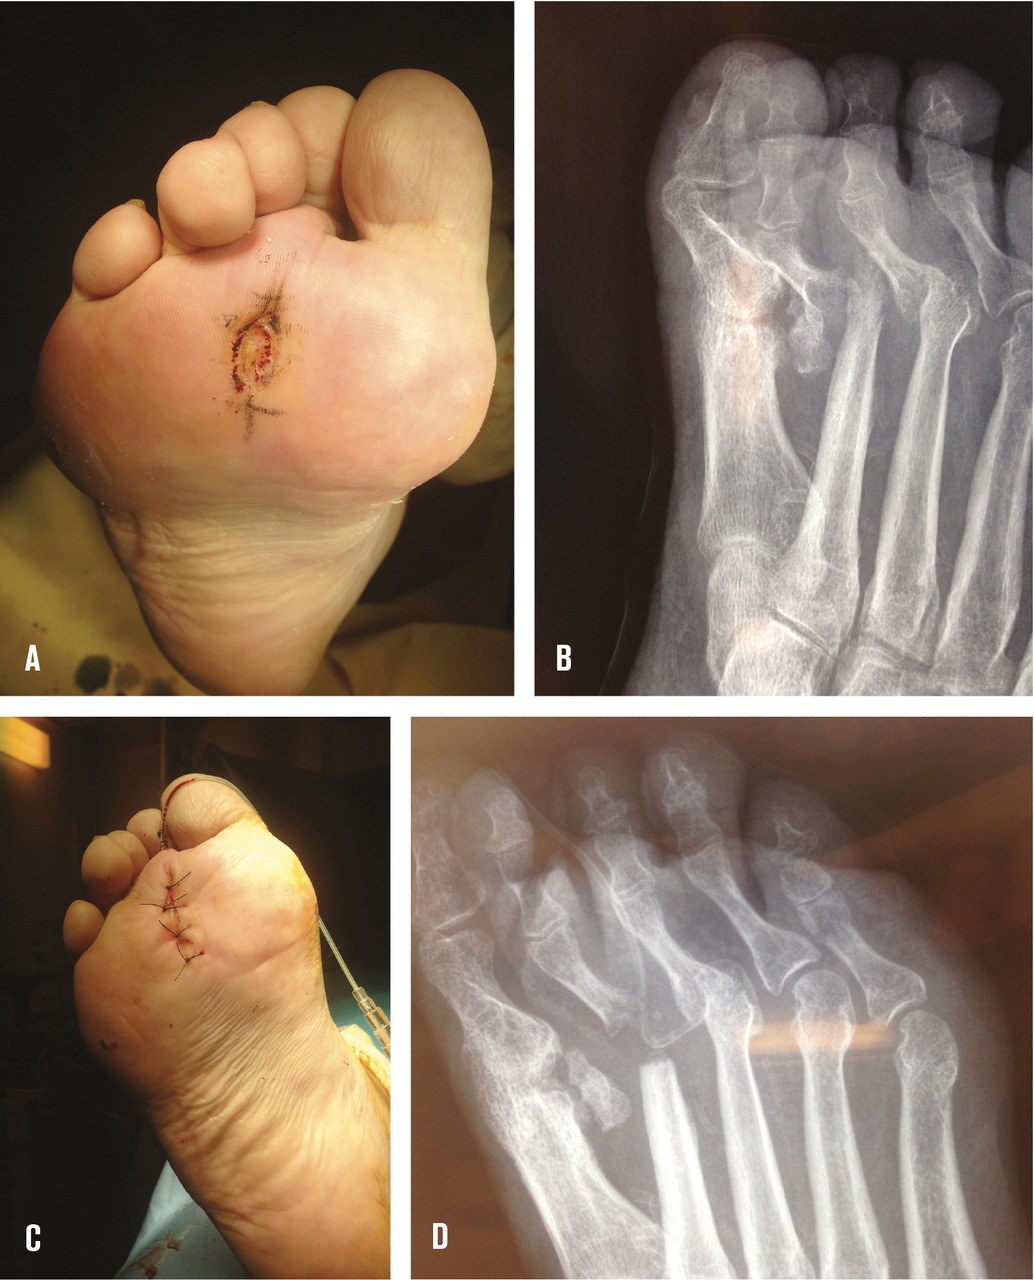

Les ostéo-arthrites métatarso-phalangiennes nécessitent la plupart du temps une résection de la tête métatarsienne (fig. 2 ) car celle-ci est le plus souvent de qualité médiocre avec un cartilage qui se décolle de l’os sous-chondral et l’os lui-même a un aspect de sucre mouillé. La résection sur la base de la phalange est souvent très limitée car l’atteinte osseuse est plus modérée. Si l’os est de bonne qualité, on peut se contenter d’une simple synovectomie associée à une ablation du cartilage avec régularisation de la tête métatarsienne, ce qui permet encore plus de limiter les risques de transfert d’appui sur les têtes voisines.